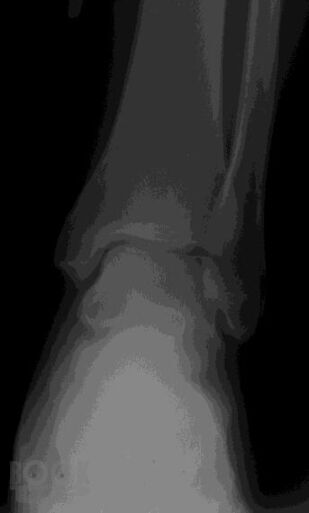

В учебном пособии представлены общие положения о развитии и анатомии опорно-двигательного аппарата, методы лучевой диагностики и показания для их использования при исследовании костей и суставов, изложены основы посиндромного подхода к диагностике заболеваний костно-суставной системы, основы диагностики травматических повреждений.